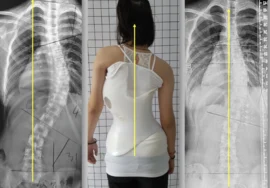

يعاني بعض المراهقات من انحناء غير طبيعي للعمود الفقري يُعرف بـ اعوجاج العمود الفقري. غالبًا ما يلجأ الأطباء إلى الحزام الطبي كحل غير جراحي لتقويم الانحناء ومنع تفاقمه.

الدراسات أظهرت أن نقص الوزن يقلل من قدرة الحزام الطبي على تقويم العمود الفقري. السبب بسيط: العضلات والأنسجة الداعمة تكون أقل سمكًا، ما يجعل الحزام أقل ثباتًا على الجسم. وبالتالي تقل قدرته على توجيه العمود الفقري بشكل صحيح.

التطور الكبير في تصميم الأحزمة الطبية جعل علاج اعوجاج العمود الفقري عند المراهقين أكثر نجاحًا وأقل إزعاجًا. باستخدام تقنيات التصوير الثلاثي الأبعاد والمحاكاة الرقمية، أصبح الحزام أكثر خفة وراحة، ويعطي نتائج أفضل في تصحيح الانحناء والتواء العمود الفقري.